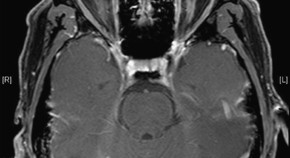

Ophthalmic findings are common features of neurodegenerative disorders, and have emerged as potentially useful biomarkers of disease progression in several conditions. Kersten et al. describe the various afferent visual system and other ophthalmic features of inherited neurodegenerative disorders, focusing on the expanding role of optical coherence tomography in diagnostic imaging of the retina and optic nerve head. They also discuss the ophthalmic manifestations and treatment implications of mitochondrial dysfunction—a feature of many inherited neurodegenerative diseases.